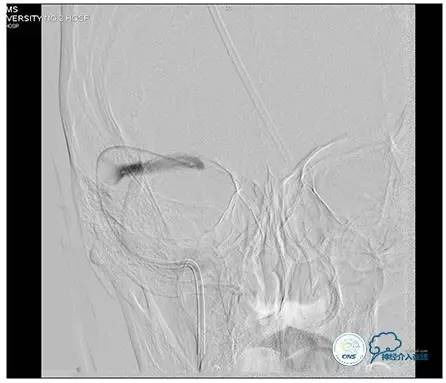

治疗方案:

1、8mm×40mm , EverCross球囊扩张;

2、8mm×40mm,Protégé自膨支架成形术。

术后右侧ICA造影

术后远、近端压力差为:0

术后右侧ICA斜位